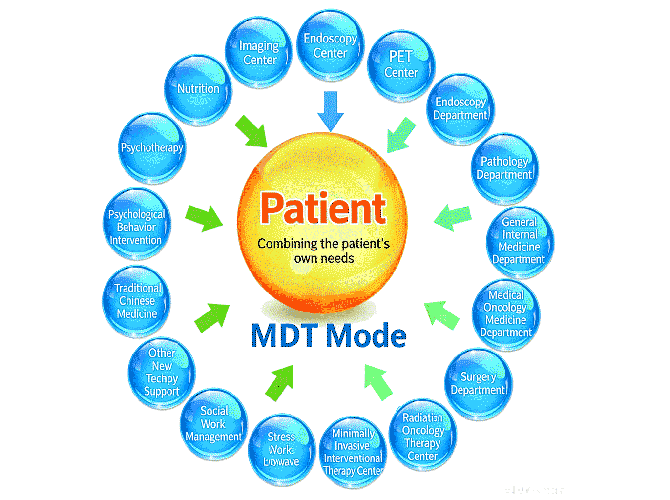

Find The Best Services You Need

Easily Book Top Specialists Near You